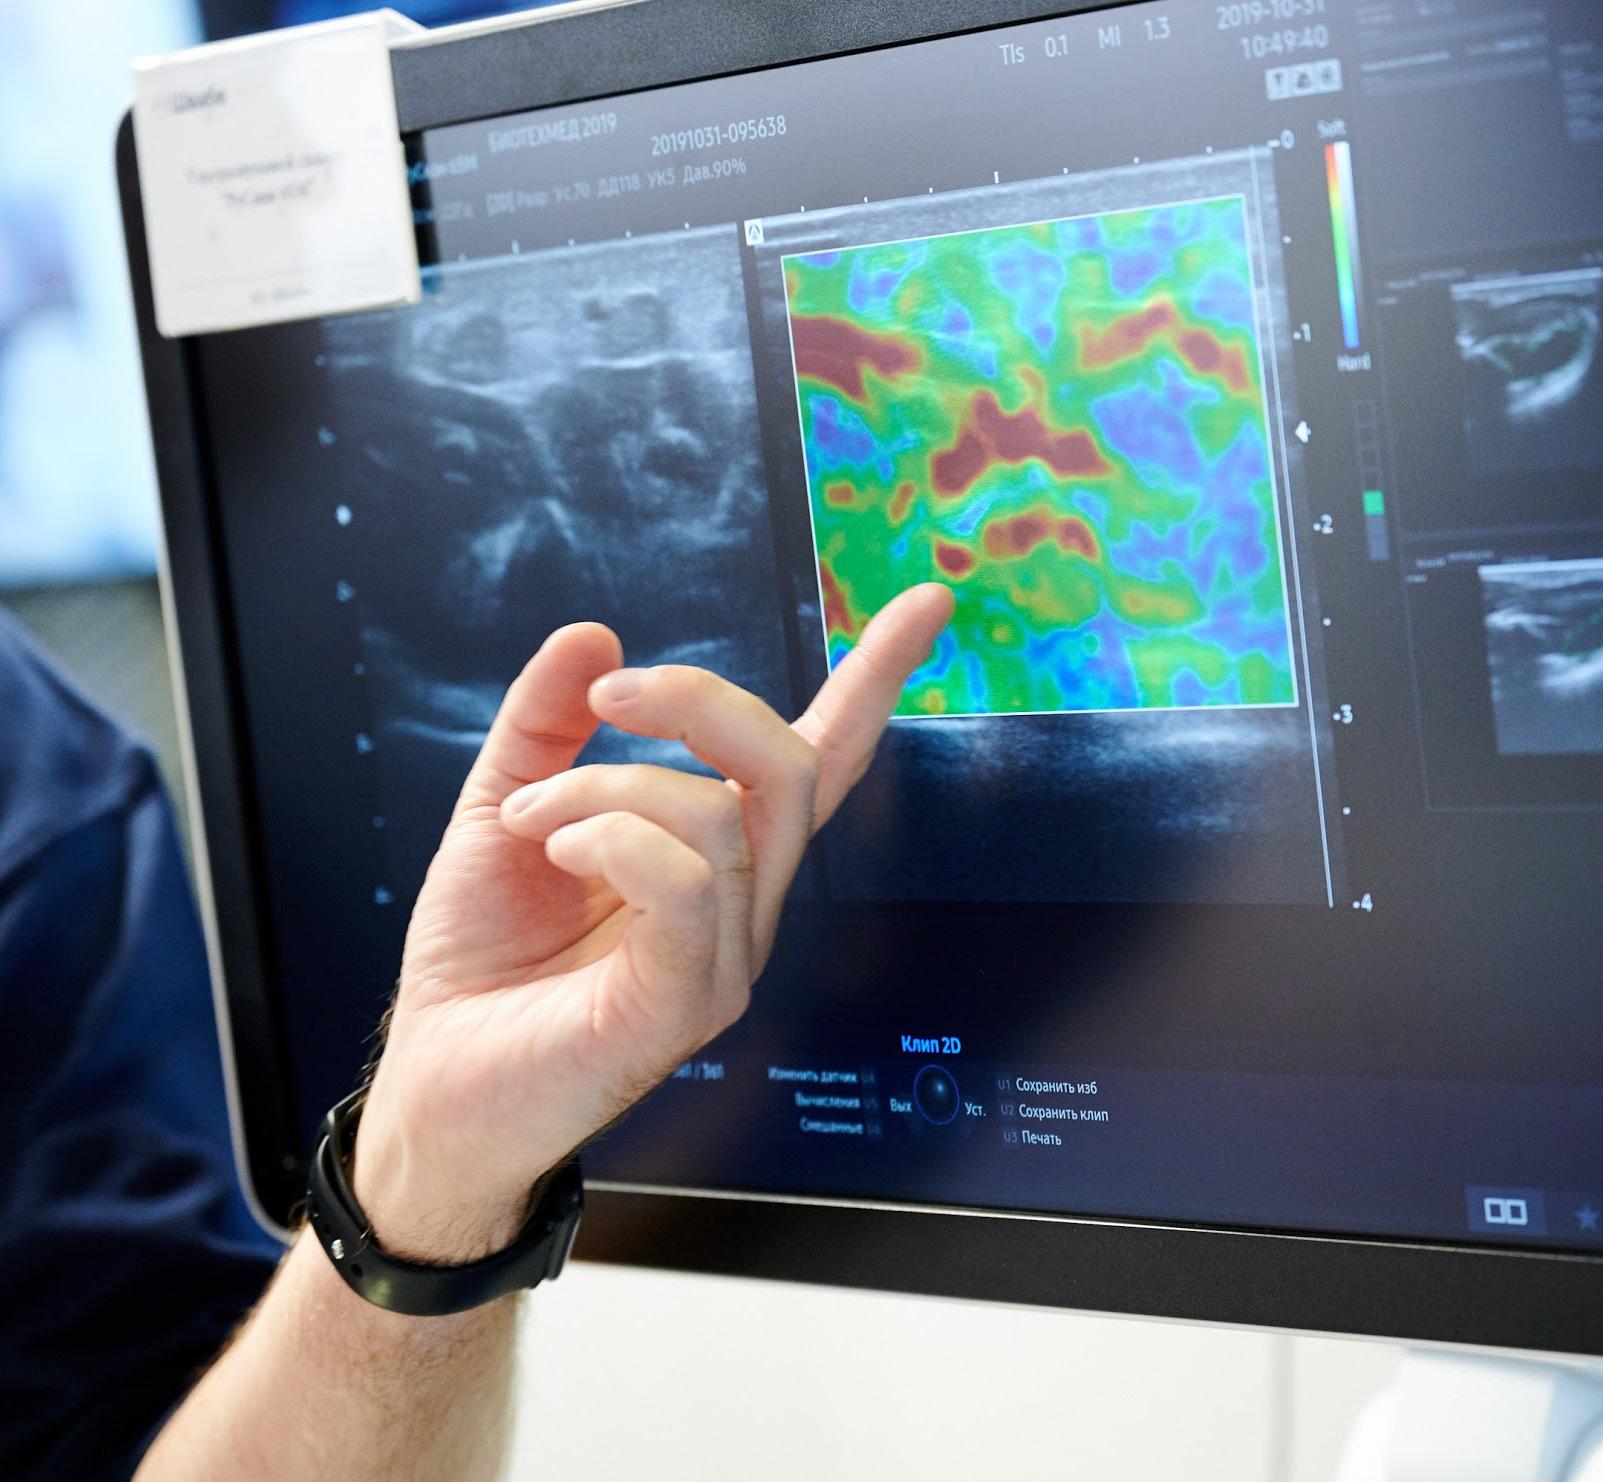

УЗИ аппараты российского производства: обзор и характеристики